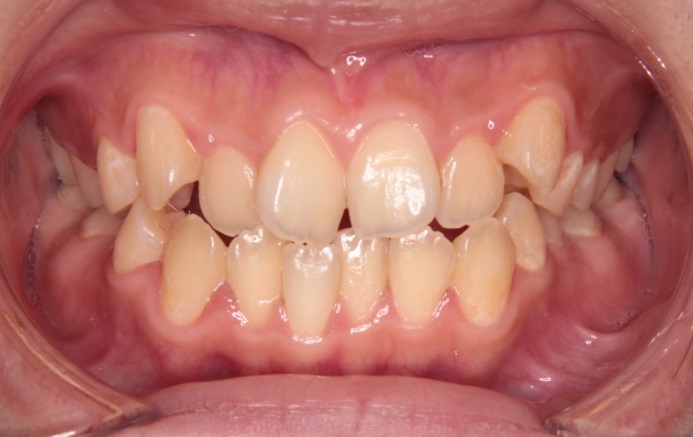

症例情報

主訴 八重歯を治したい

診断名 上下顎前歯部の叢生症例

年齢 26歳

治療に用いた装置 マルチブラケット装置

抜歯部位 上顎左右4番、下顎左右4番

治療期間 23回・2年半

治療費用 880,000円

リスク・副作用

• ブラケット装着によるカリエスリスクの上昇